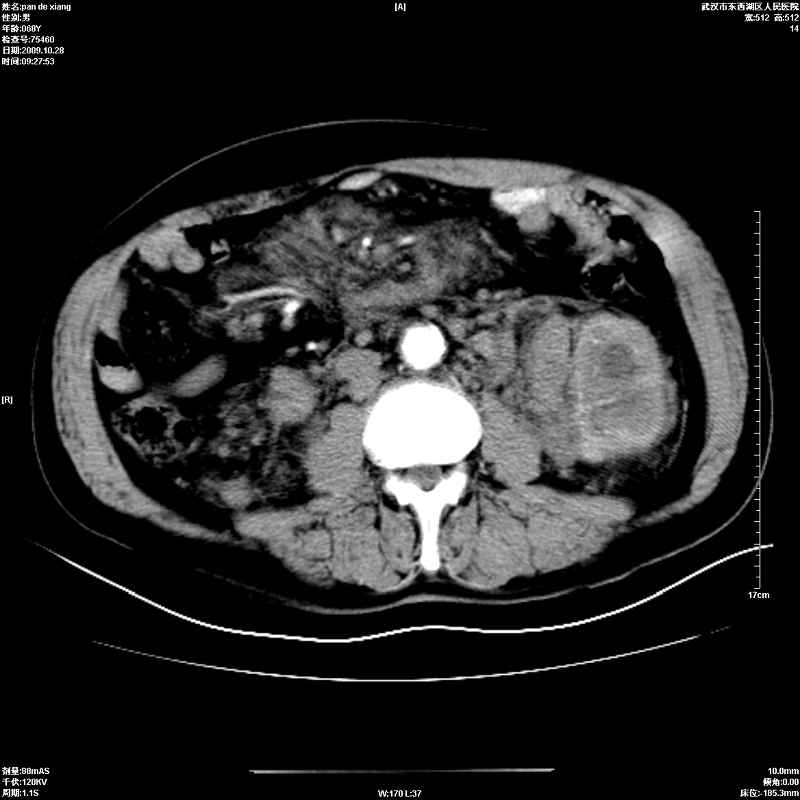

以下是引用杀毒软件在2009-10-28 20:41:00的发言:[br]结合临床考虑---白血病双肾改变或淋巴瘤。

以下是引用zxl51642在2009-10-29 9:59:00的发言:[br]结合临床“单克隆免疫球蛋白血症”,考虑双肾为继发损害并肾功能不全(尿中大量igg及少量iga、igm等大分子免疫球蛋白滤出所致继发损害),椎前软组织肿块为髓外造血。与浆细胞瘤有区别,平扫时有战友说的很清楚。